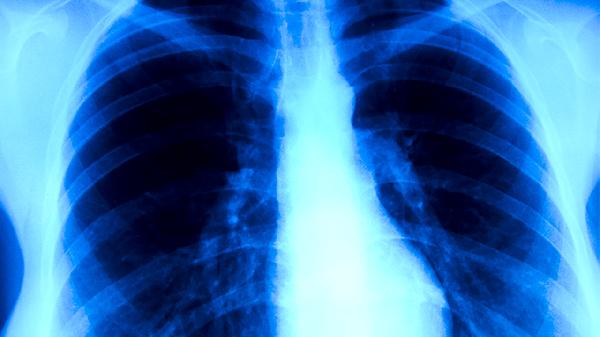

恢复期建议选择高蛋白、高维生素饮食,如鱼肉、鸡蛋、新鲜果蔬等,避免辛辣刺激食物。每日进行呼吸训练如腹式呼吸,每次10分钟,有助于改善肺功能。体温正常后仍需观察1周,若出现反复低烧或咳嗽加重,需及时复查胸片。保持充足睡眠和适度活动,避免剧烈运动诱发心肌损伤。